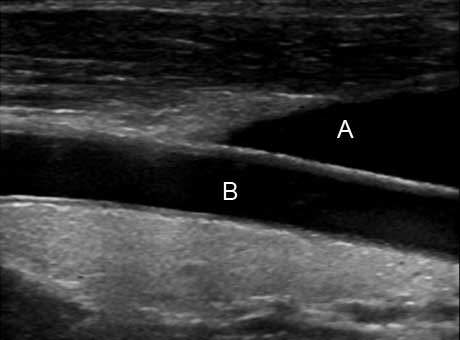

Image of carotid artery—patient lying down, head to left.

a. jugular vein

b. right common carotid artery